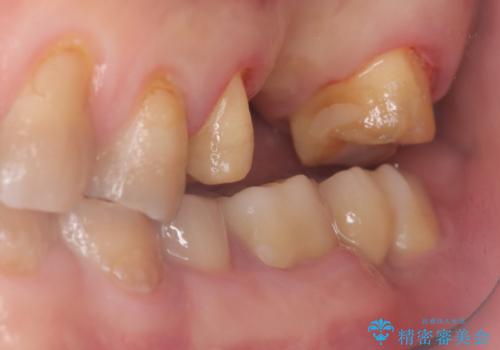

- 主訴:左上一番奥の歯の奥側にフロスを沿わせてこするといつも汚れがでてくる。

左上に保険適用の⑤ 6 ⑦ブリッジが入っており、7番目の歯と被せものとの境目に段差があり、そこに汚れが停滞したいたため適合の良いオールセラミッククラウンブリッジでのやり替えとなりました。

左上7番遠心マージン不適を認め、そこに汚れが停滞していたためやり替えをおすすめし、汚れが付着しずらく審美性に優れたセラミッククラウンブリッジでのやり替えとなりました。